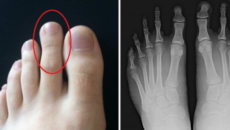

Дали спаѓате во овие луѓе? Оваа појава е распорстранета и наводно ја има секоја трета личност во Европа, но многу...